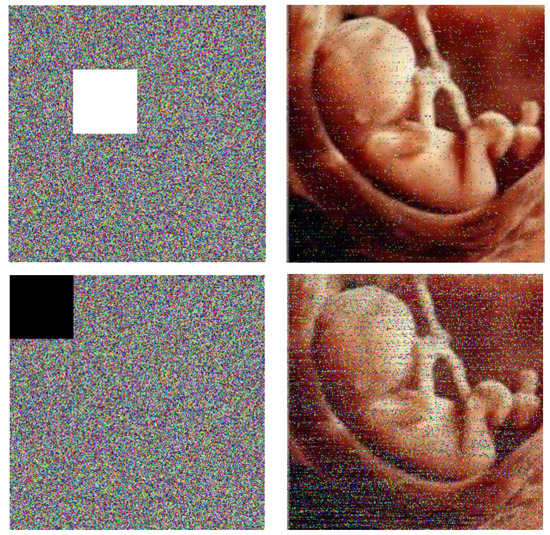

4.8. Known-Plain Image and Chosen-Plain Image Analysis

Clearly, some specific images are selected to test the selected plain-text attack, like a full-white image in Figure 8a and a full-black image in Figure 8d. The results are shown in Figure 8, which indicate that the cryptology is appropriate for these specific images and can resist the chosen-plain-text attack. In Table 6, we can see the entropy values for all-white and all-black images. It can be seen that all the values that are obtained are close to 8, indicating the suitability of the proposed algorithm.

Figure 8.

Selected plain-image test for white and black images, display (a) the full-white image, (b) the cipher image of panel (a), (c) the histogram of channel R (b), (d) the full-black image, (e) the cipher image of panel (d), and (f) the histogram of channel R.

Table 6.

Information entropy of the full-black image and full-white image.